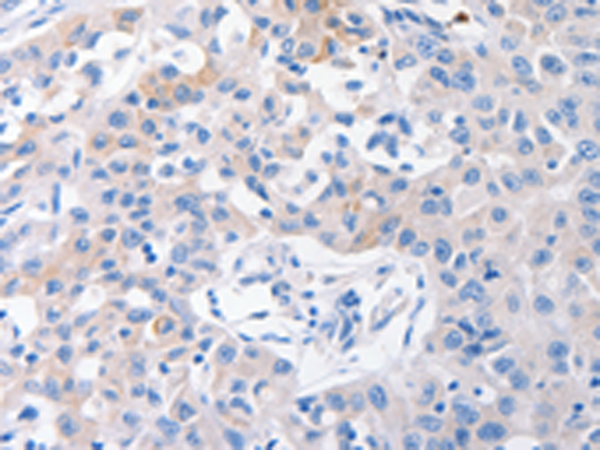

分类: 科研抗体货号: P04153别名: NTCP应用: IHC反应种属: Human, Mouse